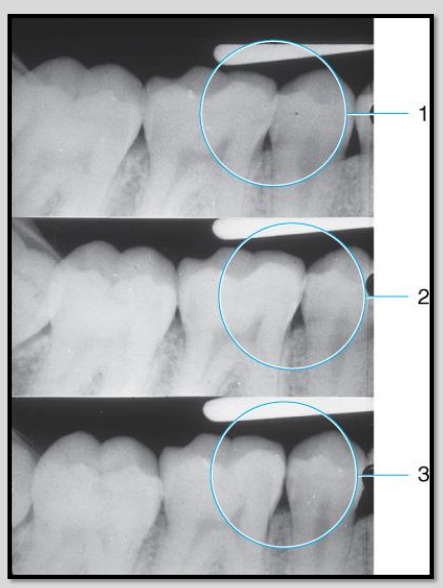

Correcting horizontal angulation for open contacts.

Open contacts are important for revealing interproximal caries.Â

Image 1 overlap hiding the cariesÂ

Image 2 has better horizontal angulation but still some overlap

Image 3 open contacts shows full extent of interproximal caries.Â